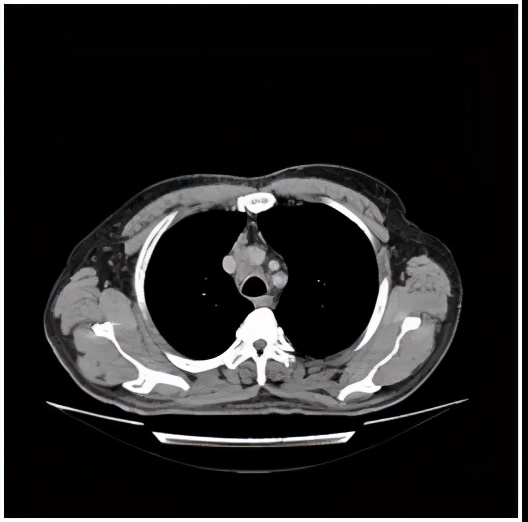

纵隔转移瘤消失